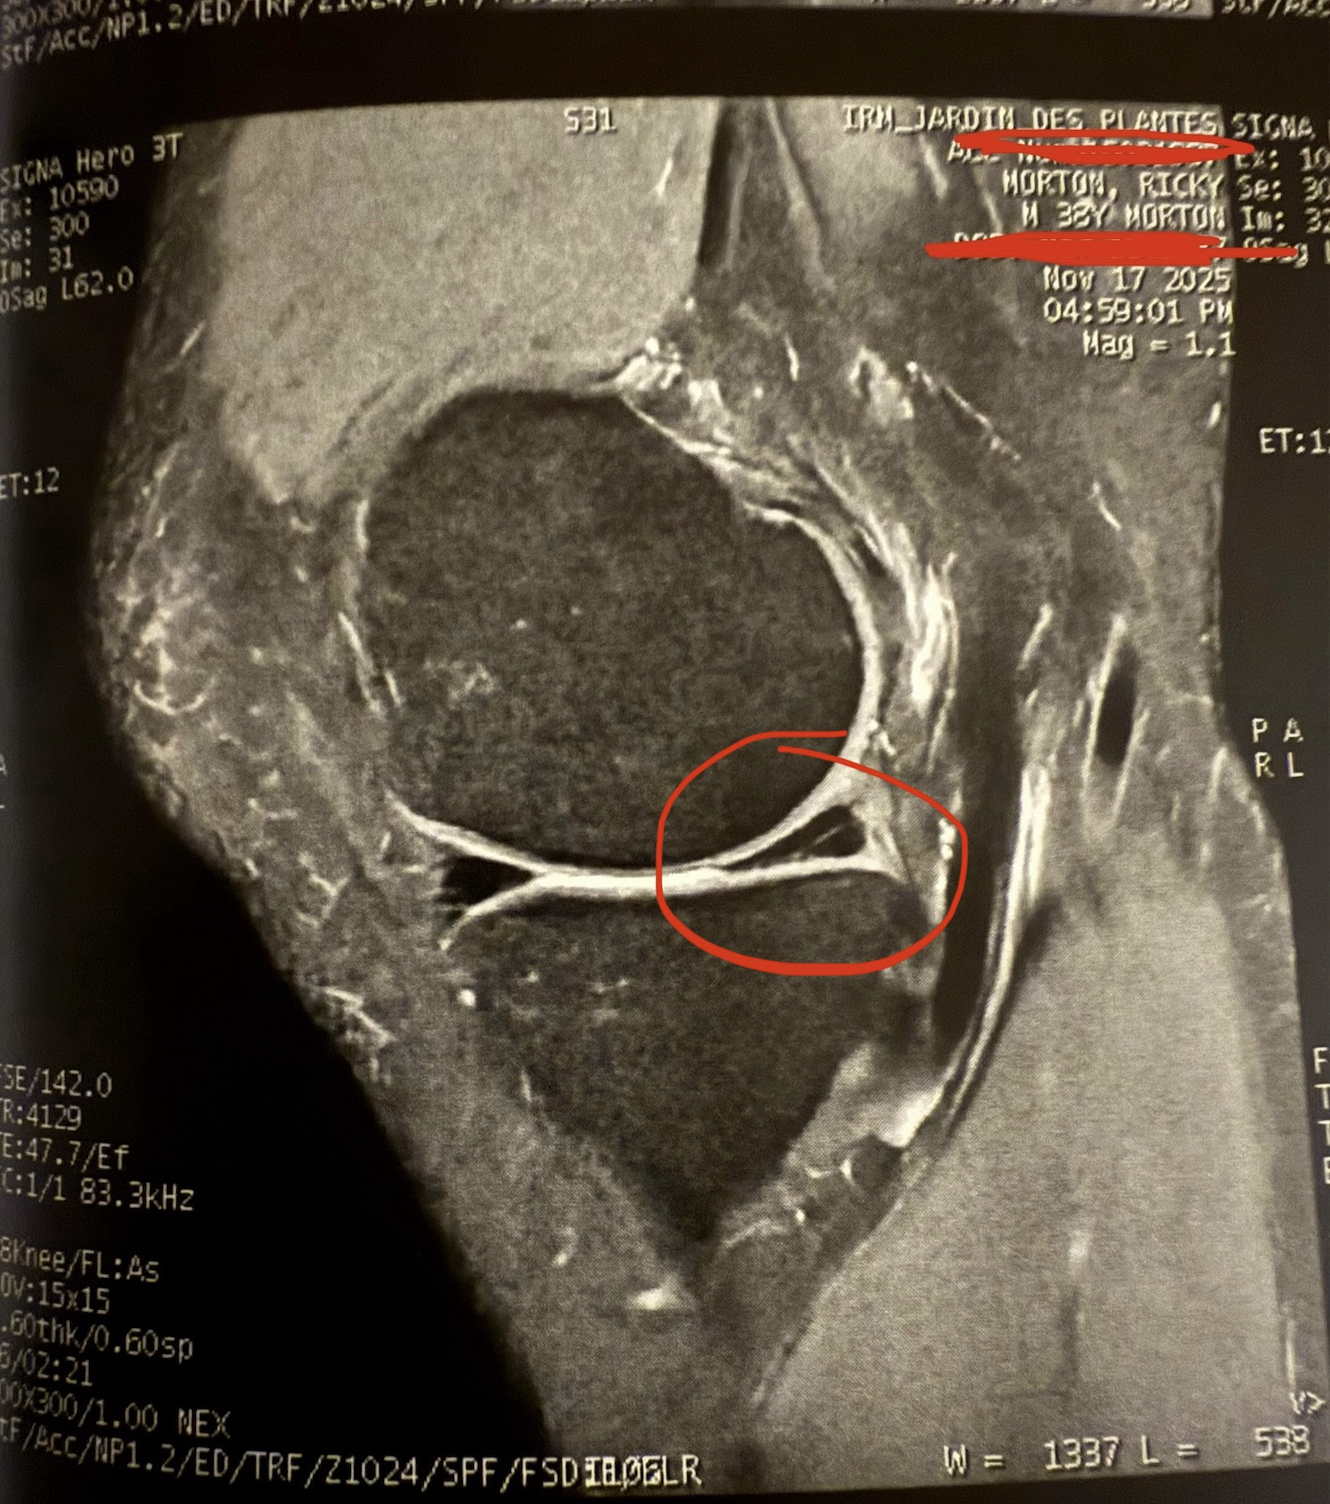

There is a logic to this, if you squint. I don't like doing any kind of admin – medical attention is admin – so if I can combine it with an activity then suddenly it becomes an adventure. And I do love an adventure, until you discover at the end of the imaging appointment that you have, in fact, torn the meniscus in your knee.

Terrible word, meniscus. The construction itself sounds like it could come apart at any moment. I can't explain this any other way except to say the word feels like two railway cars with defective coupling and it is a miracle that the two parts are even joined. How appropriate, then, that my knee has come apart. Officially. I mean, we already knew I was injured – and I am deeply sorry to write about it again, for the second time in a row – but now I knew I was injured and the knowledge was undeniable because it came with photos.

According to the doctor who interpreted the results, the injury is only a 'petite fissuration' and it came up as a thin white line, although this was two weeks and one day after it happened so God knows what I was ignoring until then.

'I don't think you will need surgery,' the doctor said, in French. The whole appointment from start to finish was conducted in French. This also made it seem like I had a petite fissuration in my brain as I contorted my facial features in a pathetic attempt to have some understanding shunted out of my mind like it was a tube that only needed to be squeezed.

Surgery! I hadn't even thought that was on the table in the first place and even though it had just been taken off the table I experienced the emotions back to front, in much the same way that I was not in an MRI clinic but an IRM clinic, per the French. What topsy-turvy world was this.